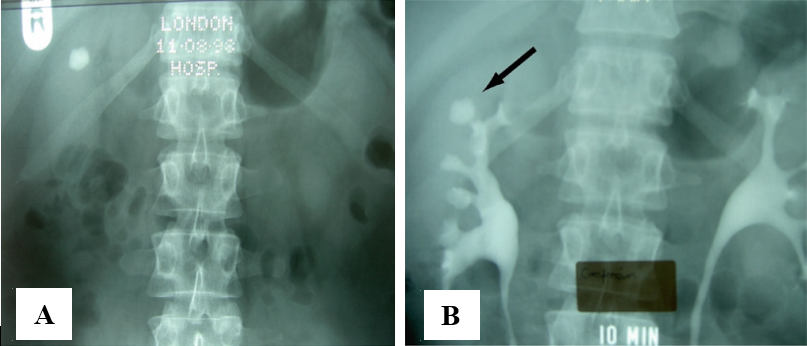

Tắc nghẽn đường tống sỏi cũng có thể là một chống chỉ định (tạm thời) đòi hỏi phải điều trị trước khi can thiệp bằng TSNCT. Những tắc nghẽn bao gồm xơ hẹp cổ đài, túi thừa đài thận (hình 5), hẹp khúc nối bể thận niệu quản, hẹp niệu quản, tăng sinh lành tính tuyến tiền liệt, hẹp niệu đạo hay hẹp miệng sáo.

8

Hình 8.Sỏi cực trên thận phải trong túi thừa đài thận

A, Phim KUB             B, Phim UIV